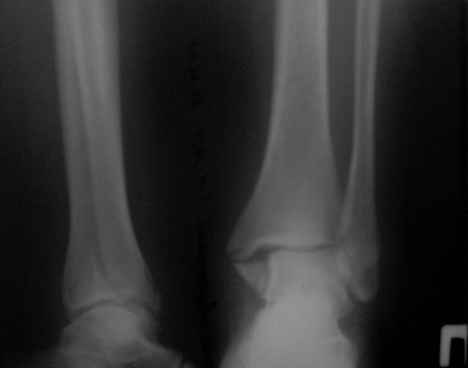

Здравствуйте,коллеги!Ко мне на консультацию обратилась больная 54 года,110 кг весом . травма 3 мес. назад , лечилась амбулаторно в гипсовой лонгете . Как поступить далее? Я планирую ORIF , внутреннюю лодыжку - спицами и проволокой , наружную - пластиной 1\3 трубки .Позиционный винт для фиксации синдесмоза. Как Вы считаете , это верная тактика ? какой вероятен исход ? Какие имеются нюансы в этом сроке , особенности техники? Может стоит вначале разработать движения в голеностопе ? Нужен ли гипс после операции ?

Имя     : первичный.jpg